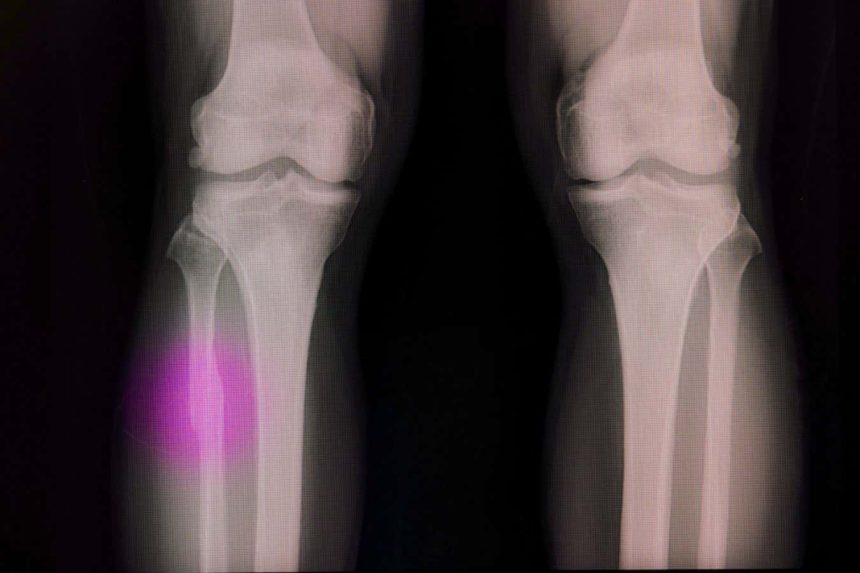

Injuries to bones often necessitate a filler material

Sopone Nawoot/Alamy

Bones possess the inherent ability to self-repair after minor injuries; however, in cases of significant trauma or surgical interventions such as tumor removals, voids need to be filled with either grafts or artificial materials that promote the proliferation of bone cells.